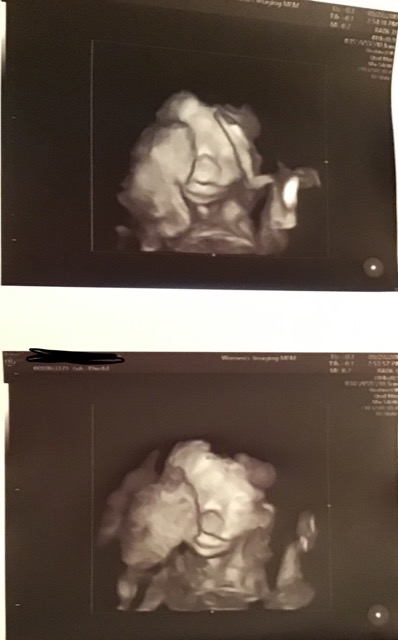

20 week ultrasound! Overbite?

We got to see our little cutie last week! I was nervous beforehand but the ultrasound tech said she looked good! So happy and relieved she is healthy! I guess what I’m wondering is how much orthodontics we are going to go through in the future because both Dad and I have overbites so I already expected our daughter to have one. Ours are not that bad though, but his sister has an extremely bad overbite and should probably have surgery because she even has trouble keeping her mouth closed.

Anyway I could tell that her chin comes back further in the profile view but is it really that much? I’ve been googling 20 week ultrasounds (I know, googling..bad lol) and most ultrasounds the chin came out more but not all of them.

Either way she’s still the cutest thing ever and I am blessed to only have to worry about this minuscule problem!